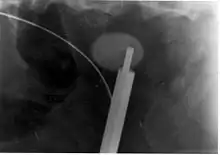

Lithotripsy

Extracorporeal shock wave lithotripsy (ESWL) is a noninvasive technique for the removal of kidney stones. Most ESWL is carried out when the stone is present near the renal pelvis. ESWL involves the use of a lithotriptor machine to deliver externally applied, focused, high-intensity pulses of ultrasonic energy to cause fragmentation of a stone over a period of around 30–60 minutes. Following its introduction in the United States in February 1984, ESWL was rapidly and widely accepted as a treatment alternative for renal and ureteral stones.[106] It is currently used in the treatment of uncomplicated stones located in the kidney and upper ureter, provided the aggregate stone burden (stone size and number) is less than 20 mm (0.8 in) and the anatomy of the involved kidney is normal.[107][108]

For a stone greater than 10 millimetres (0.39 in), ESWL may not help break the stone in one treatment; instead, two or three treatments may be needed. Some 80-85% of simple renal calculi can be effectively treated with ESWL.[7] A number of factors can influence its efficacy, including chemical composition of the stone, presence of anomalous renal anatomy and the specific location of the stone within the kidney, presence of hydronephrosis, body mass index, and distance of the stone from the surface of the skin.[106]